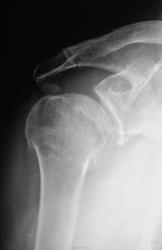

Пол пациента: Мужской пол Тип патологии: Травма Область исследования: Скелетно-мышечная система Методы исследования: Rg Травма. Пациент направлен на рентгенографию плечевого сустава. Ваше мнение уважаемые коллеги? https://radiomed.ru/sites/default/files/styles/case_slider_image/public/user/12/2.p9260006.jpg?itok=ZZgP4cVe https://radiomed.ru/sites/default/files/styles/case_slider_image/public/user/12/3.p9260006a.jpg?itok=SS2b-avQ ID:15657 Пнд, 26/09/2011 - 17:41 #1 Student_Andrew Не на сайте Был на сайте: 13 лет 8 месяцев назад Зарегистрирован: 21.08.2011 - 23:18 Публикации: 106 Вколоченный перелом хирургической шейки правой плечевой кости. Постравматическая гематома в правой аксилярной области(?) Medicus curat, natura sanat Пнд, 26/09/2011 - 20:15 #2 ДокRg Не на сайте Был на сайте: 12 лет 3 месяцев назад Зарегистрирован: 30.03.2011 - 20:05 Публикации: 105 Похоже на патологический.... Пнд, 26/09/2011 - 21:33 #3 Петрович Не на сайте Был на сайте: 7 лет 2 месяцев назад Зарегистрирован: 22.03.2009 - 01:13 Публикации: 3908 Перелом оскольчатый, а возможно, и внутрисуставной. В этом его «патологичность» Неоднозначно всё Втр, 27/09/2011 - 15:13 #4 Катенёв Валенти... Не на сайте Был на сайте: 7 лет 2 недели назад Зарегистрирован: 22.03.2008 - 22:15 Публикации: 54876 Нет, перелом не патологический - рутинный перелом.

Вколоченный перелом хирургической шейки правой плечевой кости. Постравматическая гематома в правой аксилярной области(?)

Похоже на патологический....

Перелом оскольчатый, а возможно, и внутрисуставной. В этом его «патологичность»

Нет, перелом не патологический - рутинный перелом.